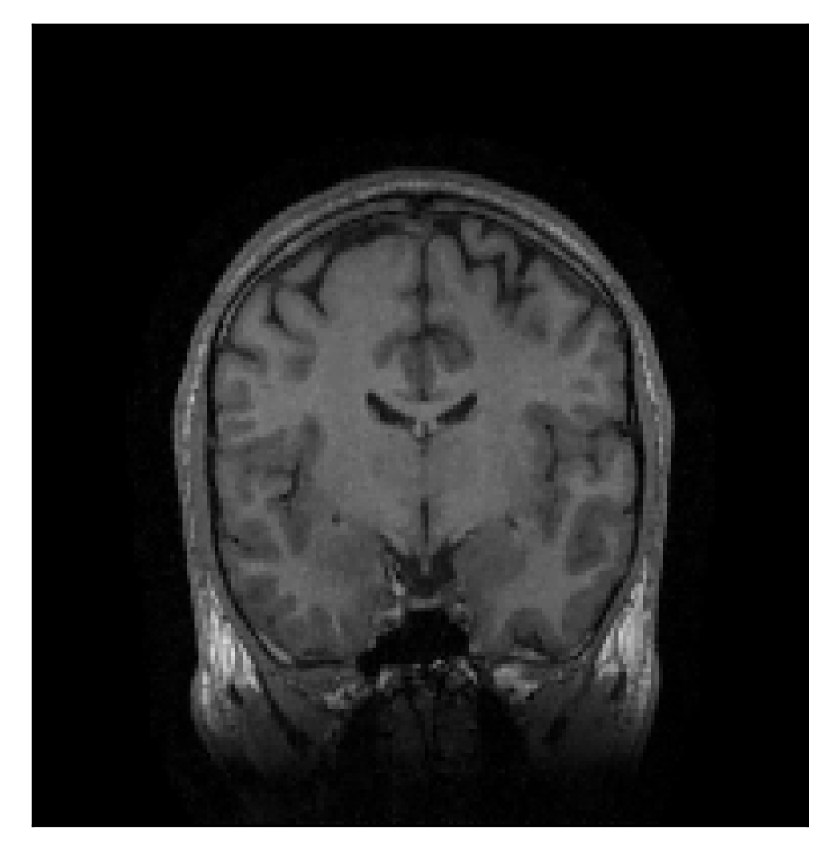

3.3 Experiment 3: scanner reconstruction vs processed raw k-space data as input for retrospective motion correction

In the first experiment, we asked volunteer 3 to change position once during the prospectively-corrupted acquisition. We consider a corrupted T2-weighted contrast and a reference T1-weighted contrast (see Table 1). One important aspect of this experiment is related to the acquisition protocol of the T2-weighted contrast, based on a linear-filling pattern in -space. The corrupted data used as input for the proposed motion-correction algorithm is obtained by exporting the reconstructed volume directly from the scanner, followed by a simple Fourier transform. Note that this 3D image has been obtained by a SENSE reconstruction.

The second experiment is set up similarly to the previous one. We asked volunteer 3 to change position only once during the acquisition phase. We consider, now, a corrupted T2-FLAIR-weighted contrast with a reference T1-weighted contrast (see Table 1). The most important difference with the previous experiment, besides the type of contrast pair considered, is related to the randomized acquisition protocol. In this case, the scanner reconstruction employs a compressed-sensing reconstruction, and is not suited as input for the proposed motion-correction algorithm (see Appendix A). Therefore, for adequate motion correction, we must set up an intermediate step for processing the raw -space data via the SENSE reconstruction.

We further discuss the results of this experiment in Section 4.3.

| Section 3.3, Figure 12 | Sagittal | 22.26 | 27.54 | 0.6963 | 0.8409 |

| Coronal | 23.46 | 31.65 | 0.7321 | 0.8370 | |

| Axial | 24.55 | 32.33 | 0.7895 | 0.8144 | |

| Section 3.3, Figure 14 | Sagittal | 24.72 | 28.76 | 0.6762 | 0.7818 |

| Coronal | 25.95 | 29.54 | 0.7238 | 0.8107 | |

| Axial | 25.08 | 29.59 | 0.7263 | 0.8407 | |

The motion-corrected full-volume scans were analyzed by a neuroradiologist with 16 years of experience. These were generally deemed of good radiological quality. The motion-related artifacts have been completely removed, and the results are quite close to the ground truth. In Table 3, we organized a more detailed qualitative analysis of the 3D results, geared toward a radiological assessment of the corrected scans.

| Experiment | Contrast | Motion resolution | Blurring | Artifacts | Additional comments |

| Section 3.3, Figure 12 | T2 | Completely corrected | No blurring | No additional artifacts | |

| Section 3.3, Figure 14 | T2-FLAIR | Completely corrected | Some blurring | No additional artifacts | Good grey white matter differentiation |

4.3 Experiment 3: scanner reconstruction vs raw k-space data

The results of the two experiments described in Section 3.3 are depicted in Figures 12 and 14. The main difference between the two experiments is related to the input data for the proposed motion-correction algorithm.

In the first experiment, the corrupted contrast has been acquired with a protocol based on a linear filling pattern in -space. Note that, in this particular case, the scanner reconstruction implements the SENSE method. We then extracted the DICOM of both amplitude and phase produced by the scanner, and used it as input data (after a Fourier transform) for the algorithm. The proposed scheme is able to successfully remove the motion artifacts in Figure 12.

In the case of randomized sampling, the scanner reconstruction is not adequate as input data for the proposed motion-correction algorithm, because it employs a compressed-sensing algorithm. We speculate that compressed-sensing reconstructions degrade the information contained in the corrupted volume, and the corrected contrast cannot be effectively recovered by simply removing rigid-motion artifacts (we defer the degraded results when using scanner reconstruction data in Appendix A). However, when the input data is obtained by directly processing the raw -space data via the SENSE reconstruction, the motion-correction scheme is able to successfully remove the motion artifacts (Figure 14).

A significant part of our experimentation was devoted to assess whether the scanner reconstruction (available as DICOM format) can be directly used as input data for the proposed correction method (Section 4.3). We established that the scanner reconstruction is not suitable for this purpose when it is obtained via compressed-sensing algorithms (Appendix A), which is the case for randomized sampling on the 1.5 T Philips Ingenia scanner utilized in this work. In this case, we must resort to the raw -space data and perform an intermediate SENSE reconstruction for effective motion correction.

Sagittal

Coronal

Axial

Axial detail

Sagittal

Coronal

Axial

Axial detail